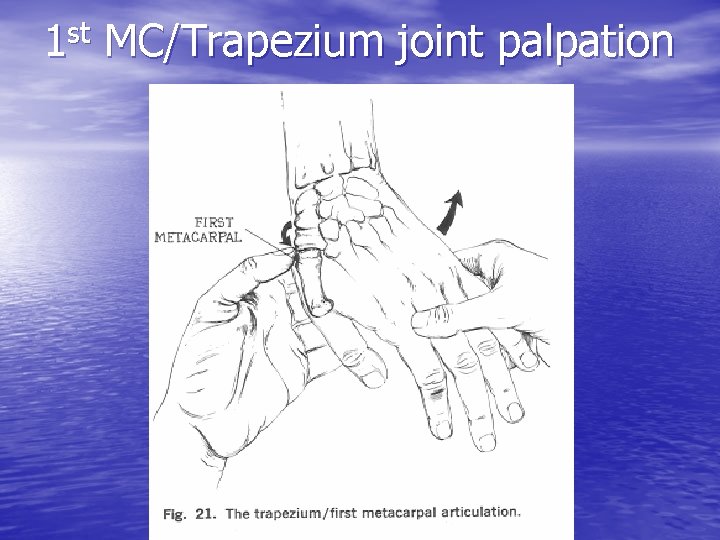

st 1 MC/Trapezium joint palpation

Thumb CMC Joint Arthritis • Painful pinch or • grasp “Grind Test” – Axial pressure to thumb while palpating CMC joint